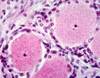

Dorsal Root Ganglion

Dorsal Root Ganglion

Dorsal Root Ganglion